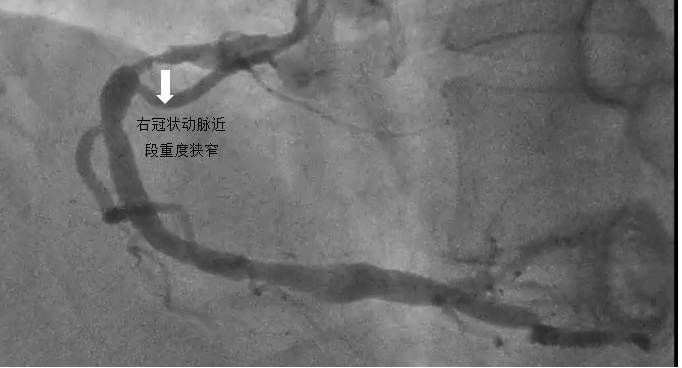

1.患者邓某,60岁,合并高血压、肥胖等多年,因主诉“反复胸痛4月”入院。患者4个月前逐渐出现活动、劳力或者紧张诱发的心前区闷痛,休息可逐渐缓解。1个月前已在我院行冠脉造影显示三支血管显著狭窄病变(左前降支90%狭窄、左回旋支70%狭窄、右冠状动脉90%狭窄)。首次介入治疗开通左前降支并植入一枚支架,术后规律冠心病二级预防治疗,计划1个月后择期介入手术开通右冠状动脉。

病例1

冠状动脉造影提示右冠状动脉近段重度狭窄

利用球囊扩张后,植入一枚药物洗脱支架,狭窄基本消失